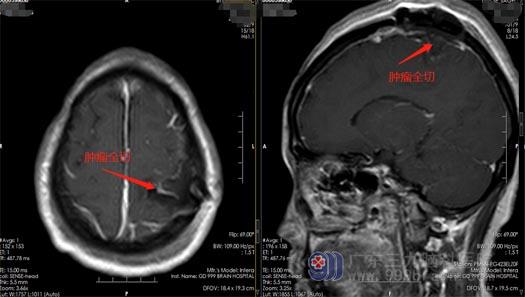

为寻求更好的手术治疗效果,查先生来到了广东三九脑科医院神经外五科。充分地评估病情后,外五科手术团队在唤醒麻醉下行“左侧顶部多发脑膜瘤切除术”。术前导航定位肿瘤,打开硬膜后见肿瘤于中央后沟,小心细致地将多发肿瘤一次性全部切除。手术顺利,术后肢体运动良好。

▲术后